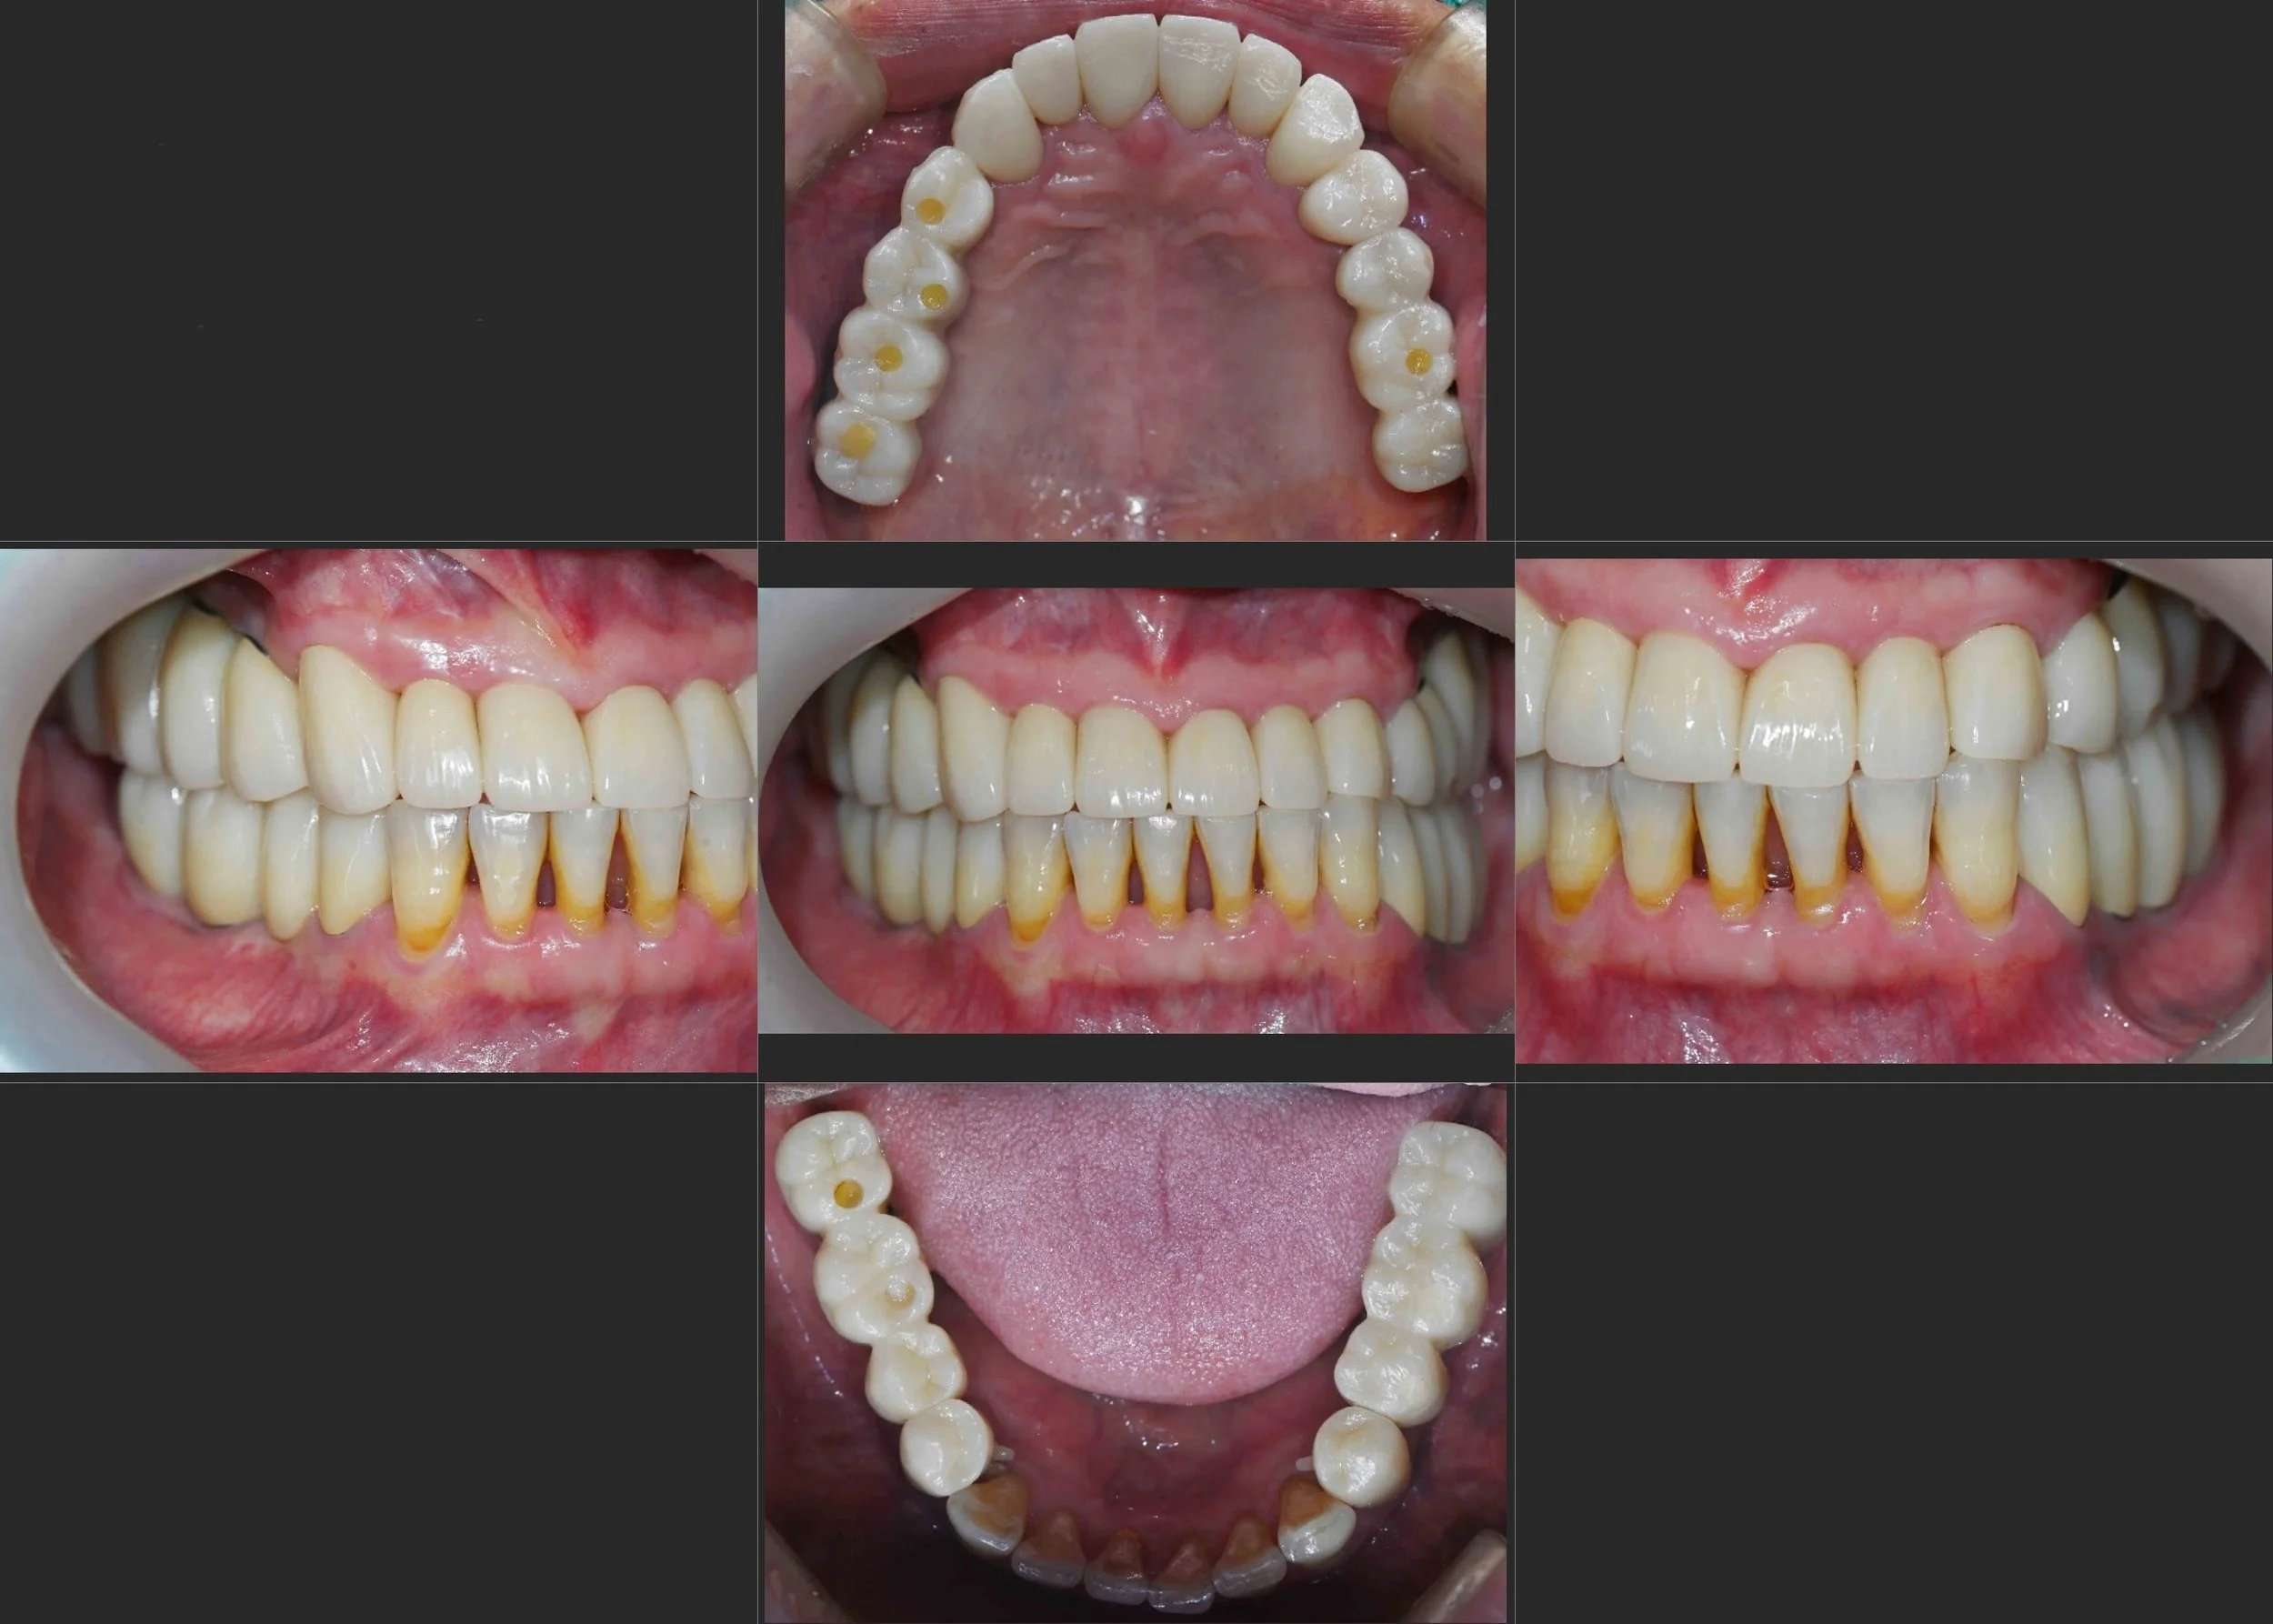

INTRA ORAL - AFTER

4. Final Delivery: Once stability was confirmed, the final implant-supported and tooth-supported prostheses were delivered. While not a "perfect" Class I occlusion, the height and positioning were meticulously set to prevent abnormal mandibular deviation, ensuring a sustainable and functional result.

The patient successfully transitioned from a state of total dental neglect and functional failure to a stable, fixed rehabilitation that has significantly improved his quality of life.